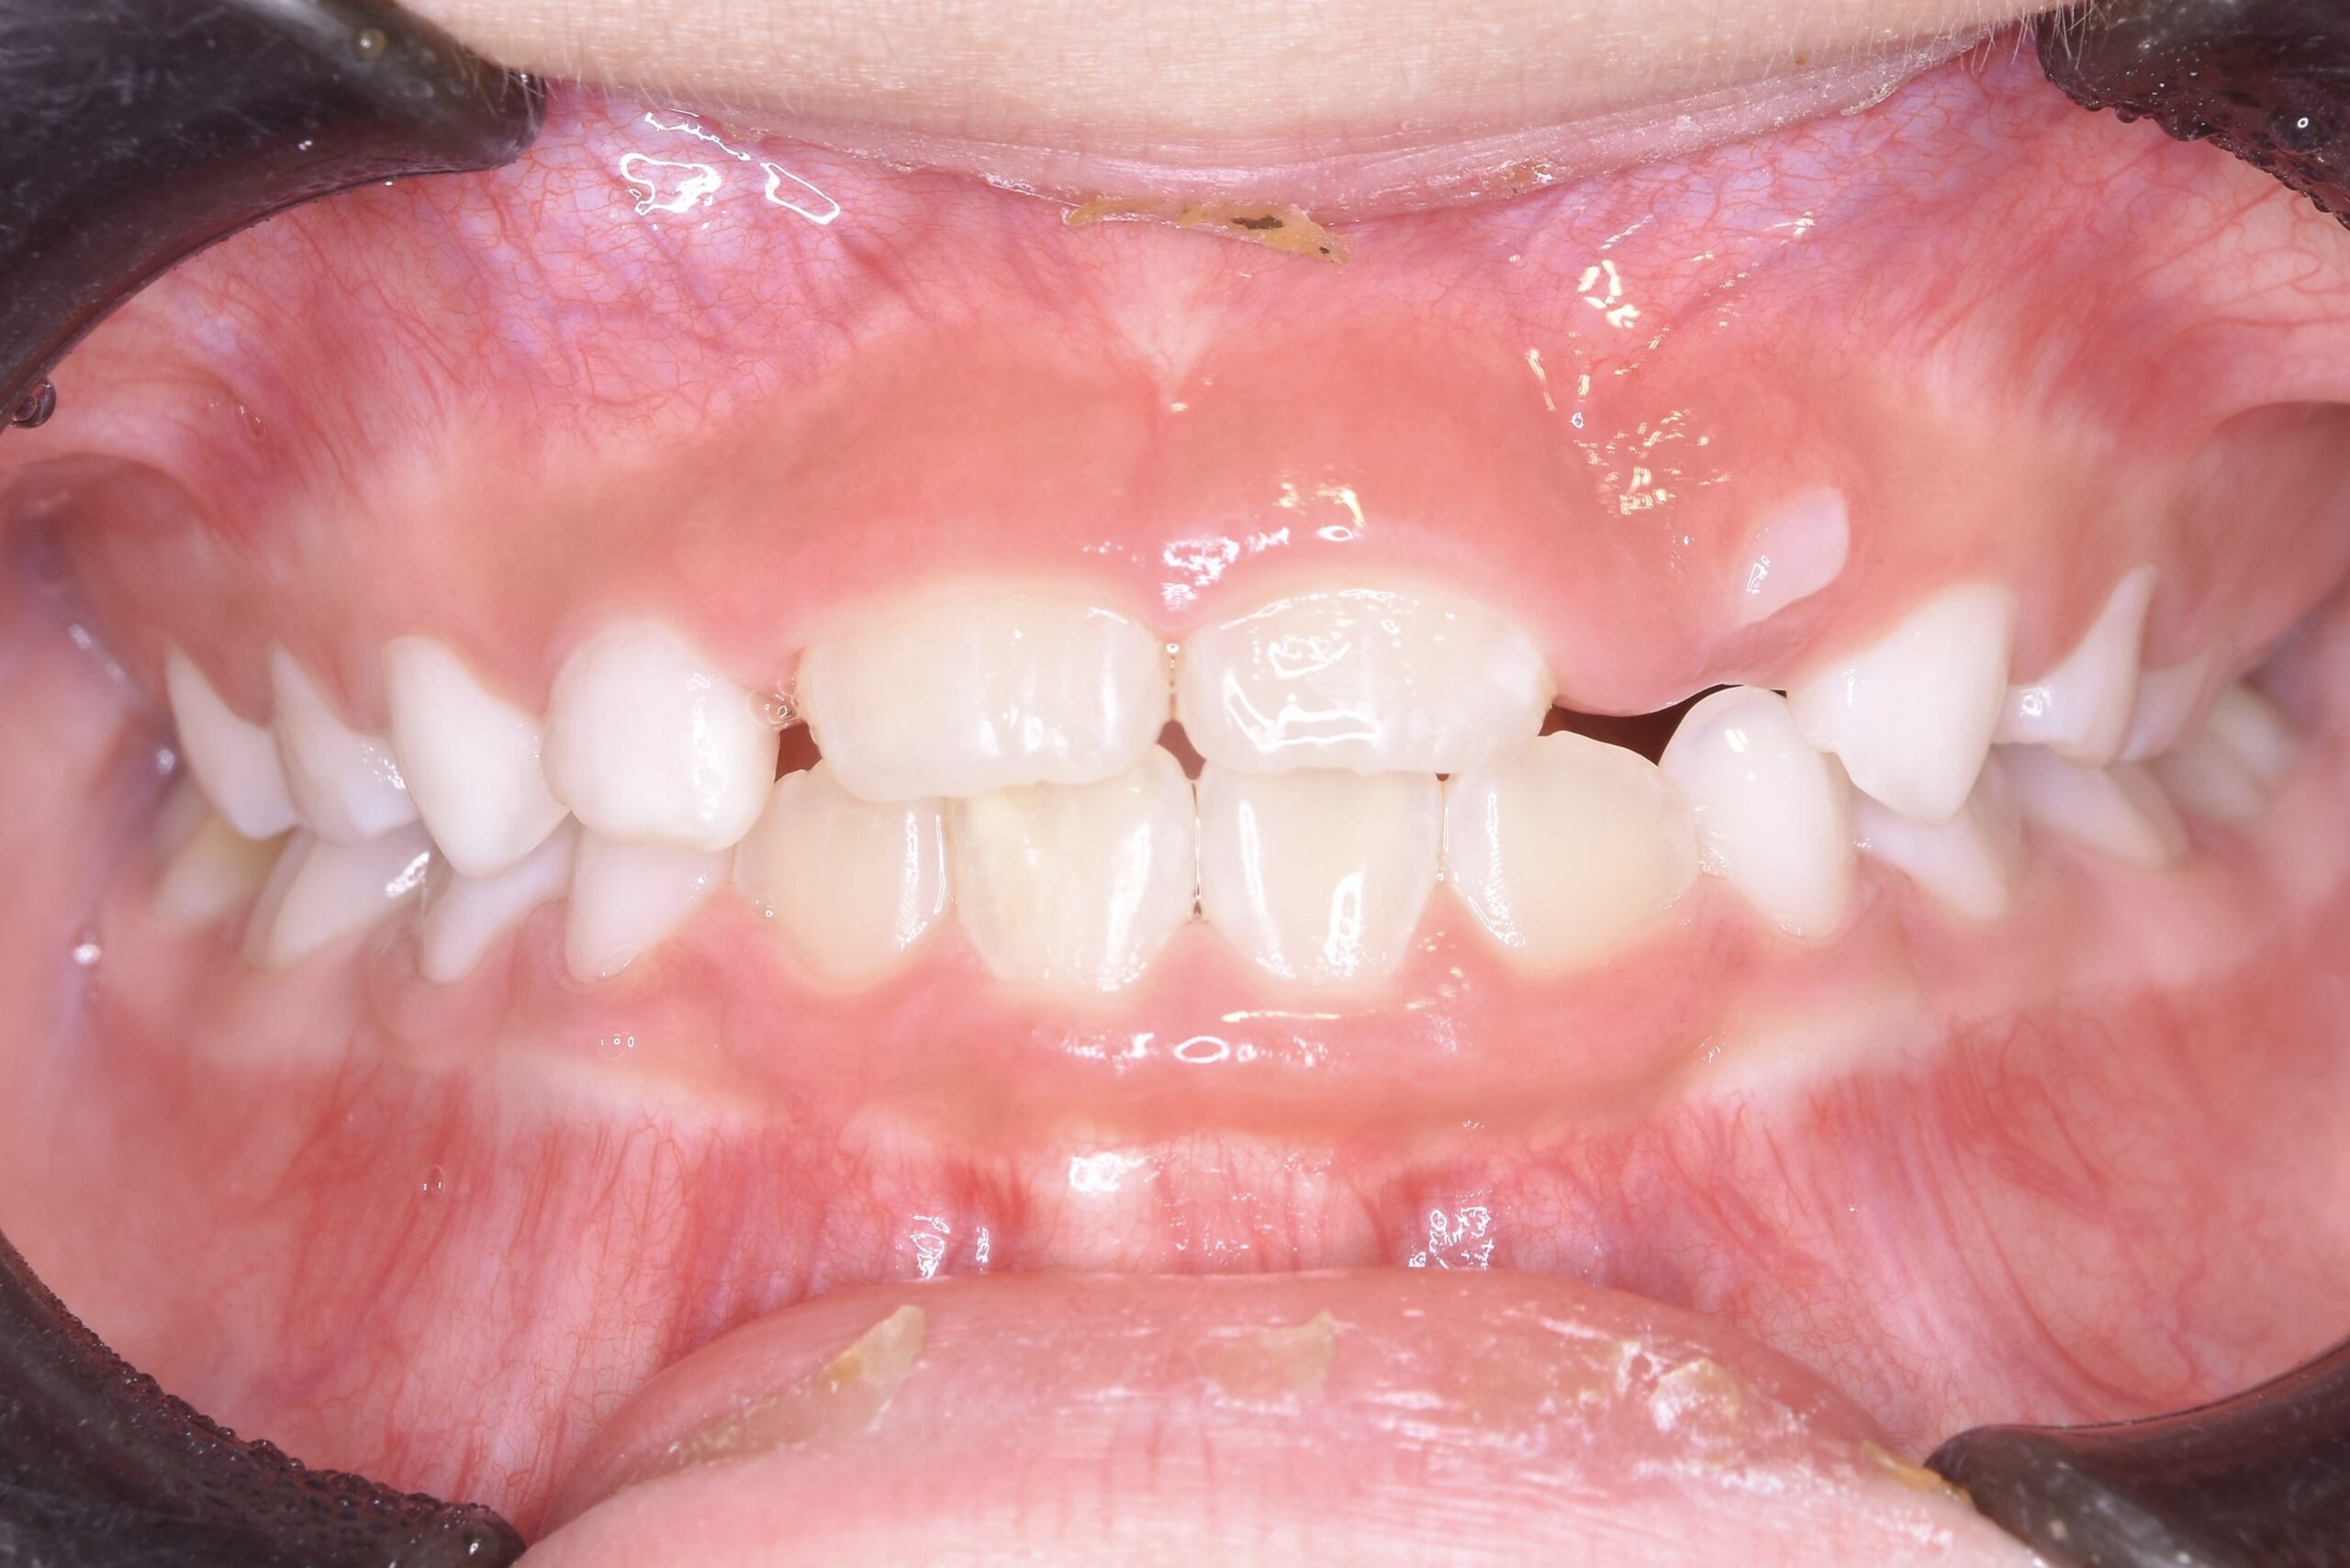

歯が生え揃う12歳頃〜成人後も

永久歯が生え揃ってから行う矯正歯科治療です。

患者様それぞれのご希望を叶えられるよう、難症例にも対応できる装置はもちろん、治療中の見た目を気にされている方も安心できる、透明で目立たないマウスピース型矯正装置もご用意しております。